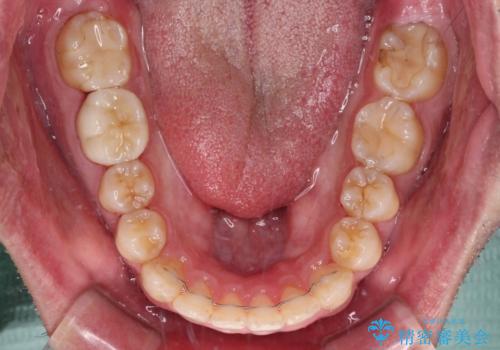

- 前歯のデコボコを治したいとのことで来院された患者様です。

できる限り楽して、短期間で治したいとのことで、ワイヤー装置にて矯正治療を行うこととしました。